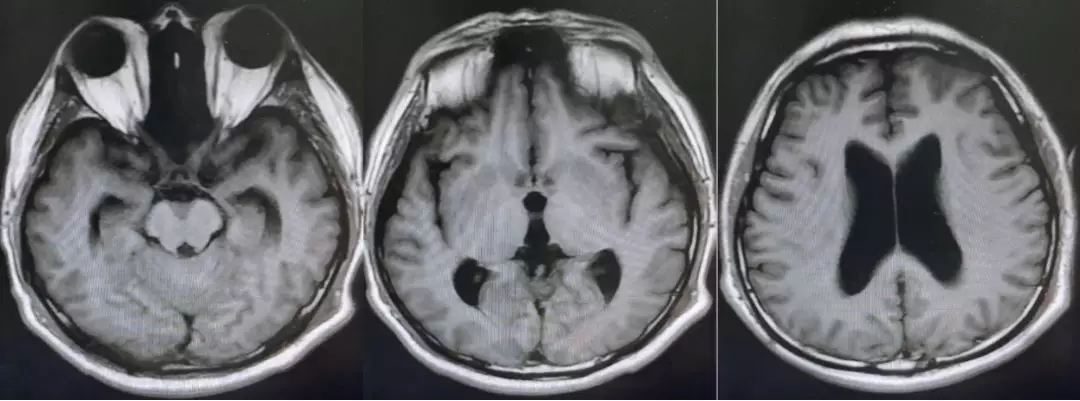

术后复查的核磁,肿瘤全切,未见残留征象。脑积水较术前改善。